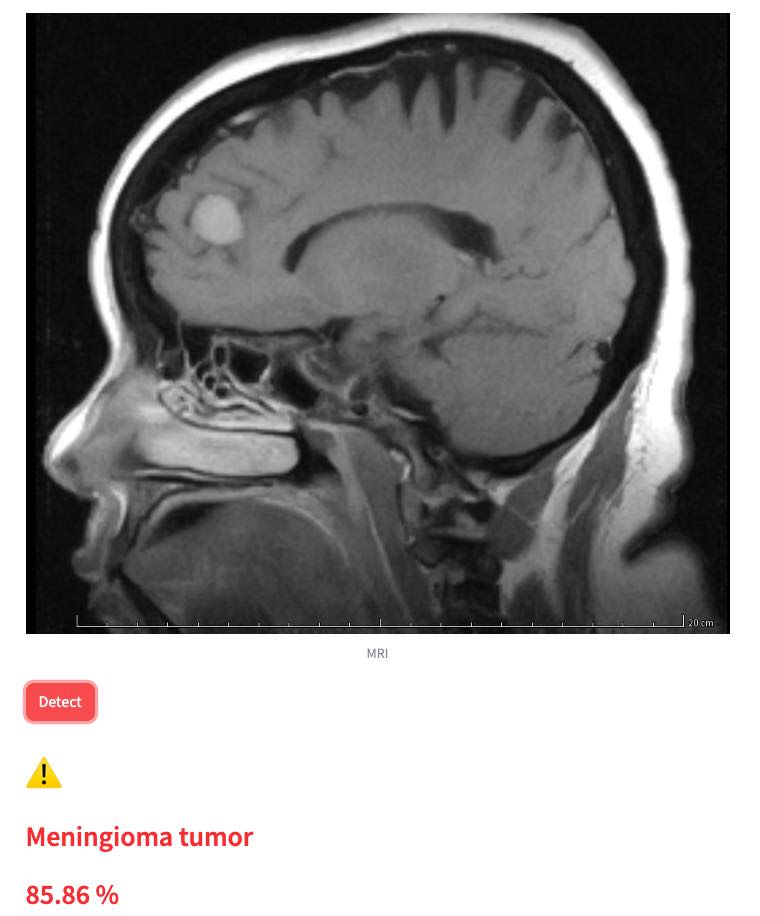

This is a human brain tumor detector app that can identify 3 types of tumor. Given a medical MRI image, app will analyse the image and return an analysed result. The result indicate whether there is a tumor detected or not with probability.

The tumor detector app include a deep learning model that was trained on a set of MRI human brain images. And the app can detect 3 type of brain cancers.

In addition it also report the probability of have any of these cancer in percentage.

The result tell you whether there is a tumor detected or not, what type of tumor and the probability.